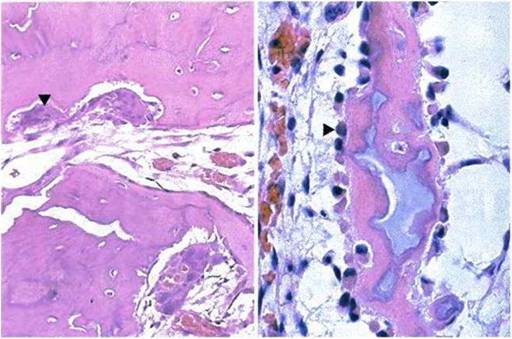

Скорость снижения двигательной активности не зависит от времени появления первых симптомов. Любой воспалительный процесс у человека с фибродисплазией может вызвать обострение и быстрое прогрессирование заболевания. Пораженные клетки проникают в мышечные ткани, ускоряя окостенение. В период дозревания образуются фиброзные волокна, формирующие бессосудистые уплотнения. Ткани, превращающиеся в хрящи, затем вступают в процесс окостенения.

- На следующей стадии формируются бессосудистые уплотнения, после чего начинается образование хрящей.

- Последней стадией является оссификация.